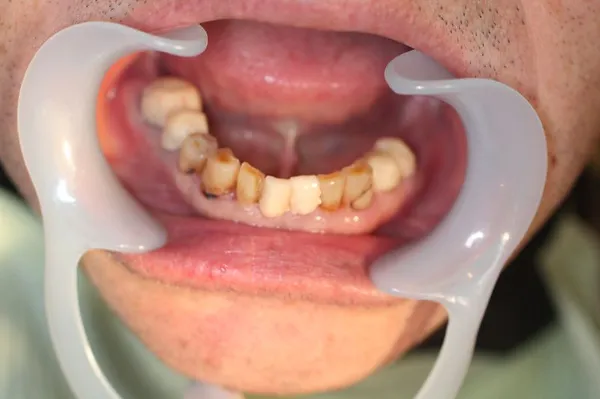

3虫歯/被せもの【虫歯の治療例1】

治療前

治療後